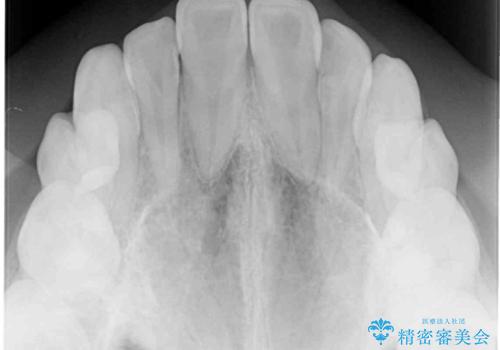

反対咬合は上顎骨の幅が下顎骨よりも小さいことが原因なので、拡大装置により骨幅を広げて上下関係を改善し、その後インビザラインにて歯並びを整えることとしました。

反対咬合が改善され、食いしばり癖もなくなり、顎関節の負担が軽減されました。